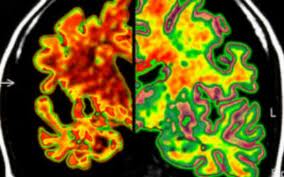

El ensayo está diseñado para probar la teoría generalizada de que la enfermedad de Alzheimer está causada por una acumulación en el cerebro de una proteína llamada beta-amiloide. El fármaco experimental – crenezumab, que está fabricado por Genentech en San Francisco – está diseñado para atacar a la formación de la placa beta-amiloide.